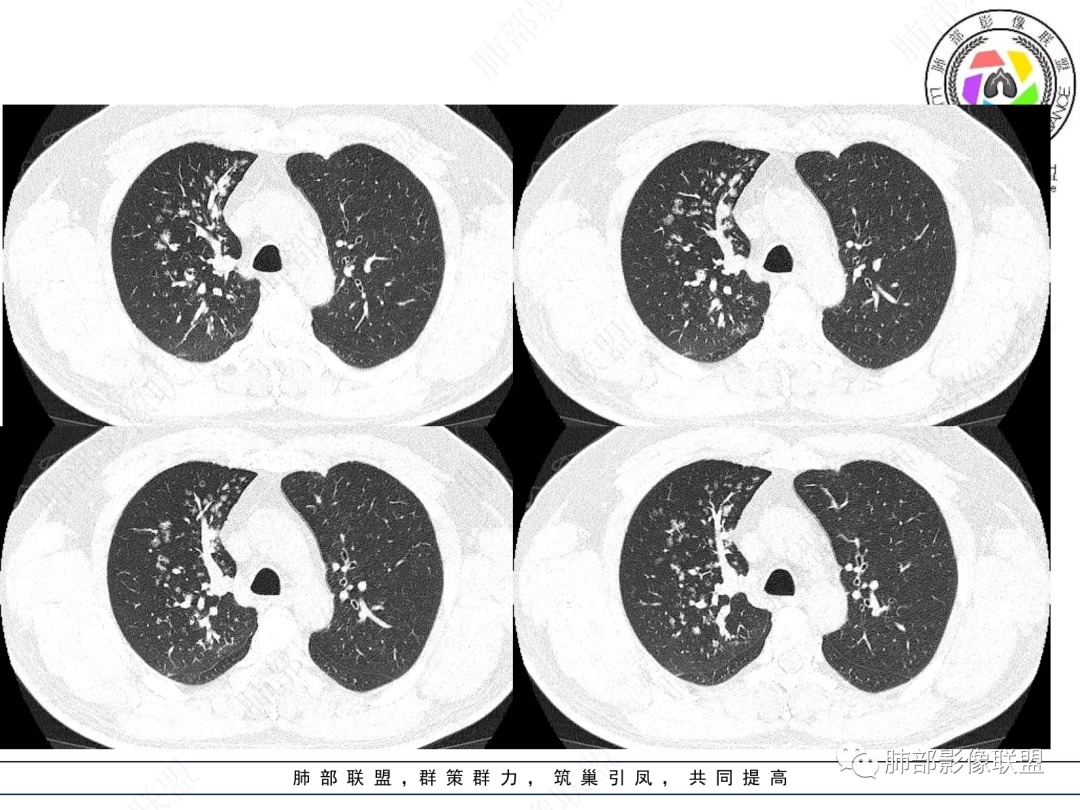

右肺上叶支气管截断,内见软组织密度结节,支气管管壁破坏,病变侵及管外,增强强化明显。右肺上叶沿气管血管束多发斑片影,考虑恶性性病变并阻塞性炎症,鳞癌,神经内分泌肿瘤。

老年男性,咳嗽咳痰,右肺门增大,右主支气管开口见高密度影,密度不均匀,轻度强化,右肺上叶见多发腺泡结节,支气管管壁增厚,近端粘液栓,支气管镜检查见新生物,考虑鳞癌,鉴别结核。

右主支气管及肺门不规则软组织结节,点状钙化,不均匀强化,气管壁破坏,上叶支气管阻塞,分支粘液栓,血管束增粗,沿支气管分布多发结节,考虑鳞癌合并阻塞性炎症,鉴别结核。

右气管腔内结节,右肺门肿物,有钙化,右侧肺内多发气腔结节,散在,左肺部分支气管壁增厚,首先分析气管内结节,多考虑1鳞癌,形态规则,边缘光滑,宽基底,不太支持,远端阻塞性炎症不典型,2类癌,冰山一角和冰山分离了,不太支持3结核,多为支气管壁广泛增厚钙化,形成结节少,但是肺门肿块有钙化,可作为结核支持点,4黏痰,不像。其他不太懂了,肺内多发磨玻璃结节,并可见支气管手指状扩张,综合分析影像,考虑感染性病变,结核?有没有这样子的气管曲霉呢?向老师们学习。

老年男性,右肺门主支气管腔内软组织肿块影,密度不均,有钙化,右上叶支气管腔部分阻塞,强化较明显,右肺上叶远端散在斑片状高密度影,相应支气管壁厚,树丫状腺泡结节,常规首先考虑结核,鉴别类癌。

男,52。间断咳嗽、咳痰2周,加重3天。胸部CT:右主、右上叶支气管多发软组织影,跳跃不连续,内可见小环状高密度,点状钙化,管壁破坏,上叶支气管堵塞,远端分支粘液栓,可见小支气管管壁增厚、管腔狭窄,沿支气管分布多发结节,无大片炎症不张。考虑:TB?NTM?鉴别Ca并阻塞性炎症。

患者中老年男性,咳嗽咳痰2周,无发热、咯血,伴胸闷、乏力及盗汗等,右上叶沿支气管血管束分布结节样变,管壁增厚;右肺门肿块,形态不规则、密度欠均匀,似有钙化,轻强化,主气道下端及右主支气管开口处见新生物,强化不支持类癌,镜下病变形态不大支持腺样囊性癌,考虑鳞癌可能性大,右肺上叶病变结核可能。

右肺上叶支气管开口见阻塞物影及强化,息肉样向腔内外浸润性生长,并有颗粒钙化,右肺上叶段支气管主干增粗及密度增高,见指套征,支气管血管旁见多发小斑点,小斑片影阻塞性炎性病灶〈小花小草表现〉,支气管镜示新生物血供丰富(结核完全排除),方向恶性,符合鳞癌特点,与小细胞Ca鉴定,临床专科支气管镜取材活检明确诊断。

一点不异常啊,分布在阻塞责任气管区域的支气管增粗伴腺泡结节(细支气管腔内及肺泡内阻塞性炎症伴痰栓),只不过还没有大片实变而已。@韩平     临沂市人民医院呼吸科

影像上分析的观察点:腔内、壁、腔外、远端,然后就是远端肺组织、淋巴结、肺血管、胸膜、其他肺部,这个人就是阻塞性炎症为主。